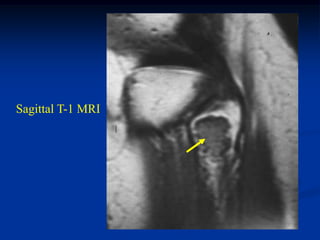

Case #551

62 year male

enchondroma

proximal humerus

Coronal T-1 MRI

CT scan